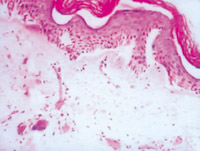

5-2-3 伤后第3天,,,,,,,表皮细胞空泡化,,,,,,,真皮浅层胶原纤维玻璃样变,,,,,,,真皮内散在炎细胞浸润  HE×100